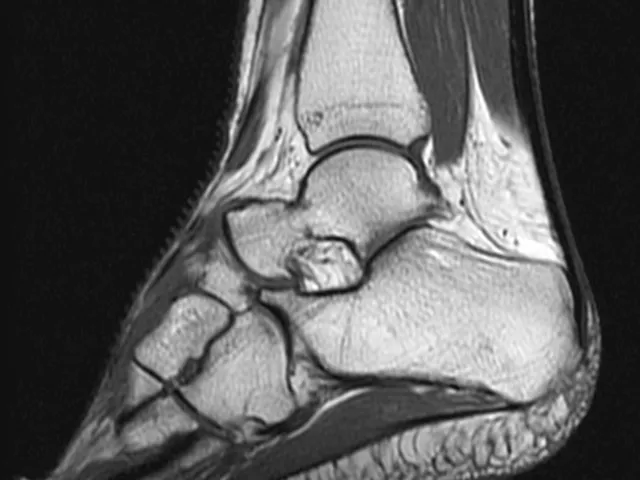

The purpose of this radiology fellowship is to discuss different LOWER EXTREMITY MSK topics and start practicing immediately by reading selected cases together with the mentor. The lower extremity module discusses the hip and pelvis, the knee, the ankle, and the foot, together with some lower extremity muscle and tendon lesions. The selected cases for reading are from our teaching file and allow the participant to practice with common cases that may appear in your daily worklist.

• Ankle and mid foot ligaments

• Flat foot of the adult